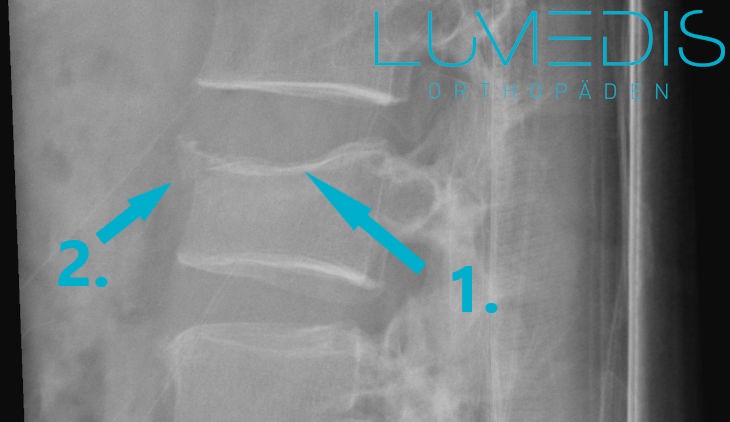

Abbildung eines gesunden Wirbels (1.) mit guter trabekulärer Struktur und eines Fischwirbels (2.)